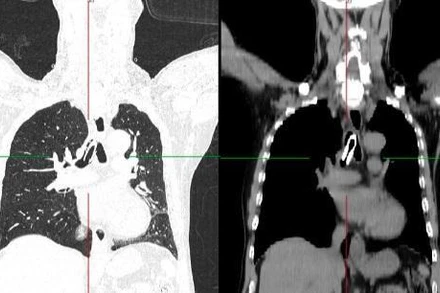

Chủ quan không đi khám, người bệnh nhập viện vì bướu giáp thòng lớn chèn ép khí quản

Bệnh nhân có u tuyến giáp nhiều năm nhưng do chủ quan và chưa thấy ảnh hưởng lớn nên chưa đi khám, chỉ đến khi cổ phình lớn, khó thở mới đến bệnh viện.